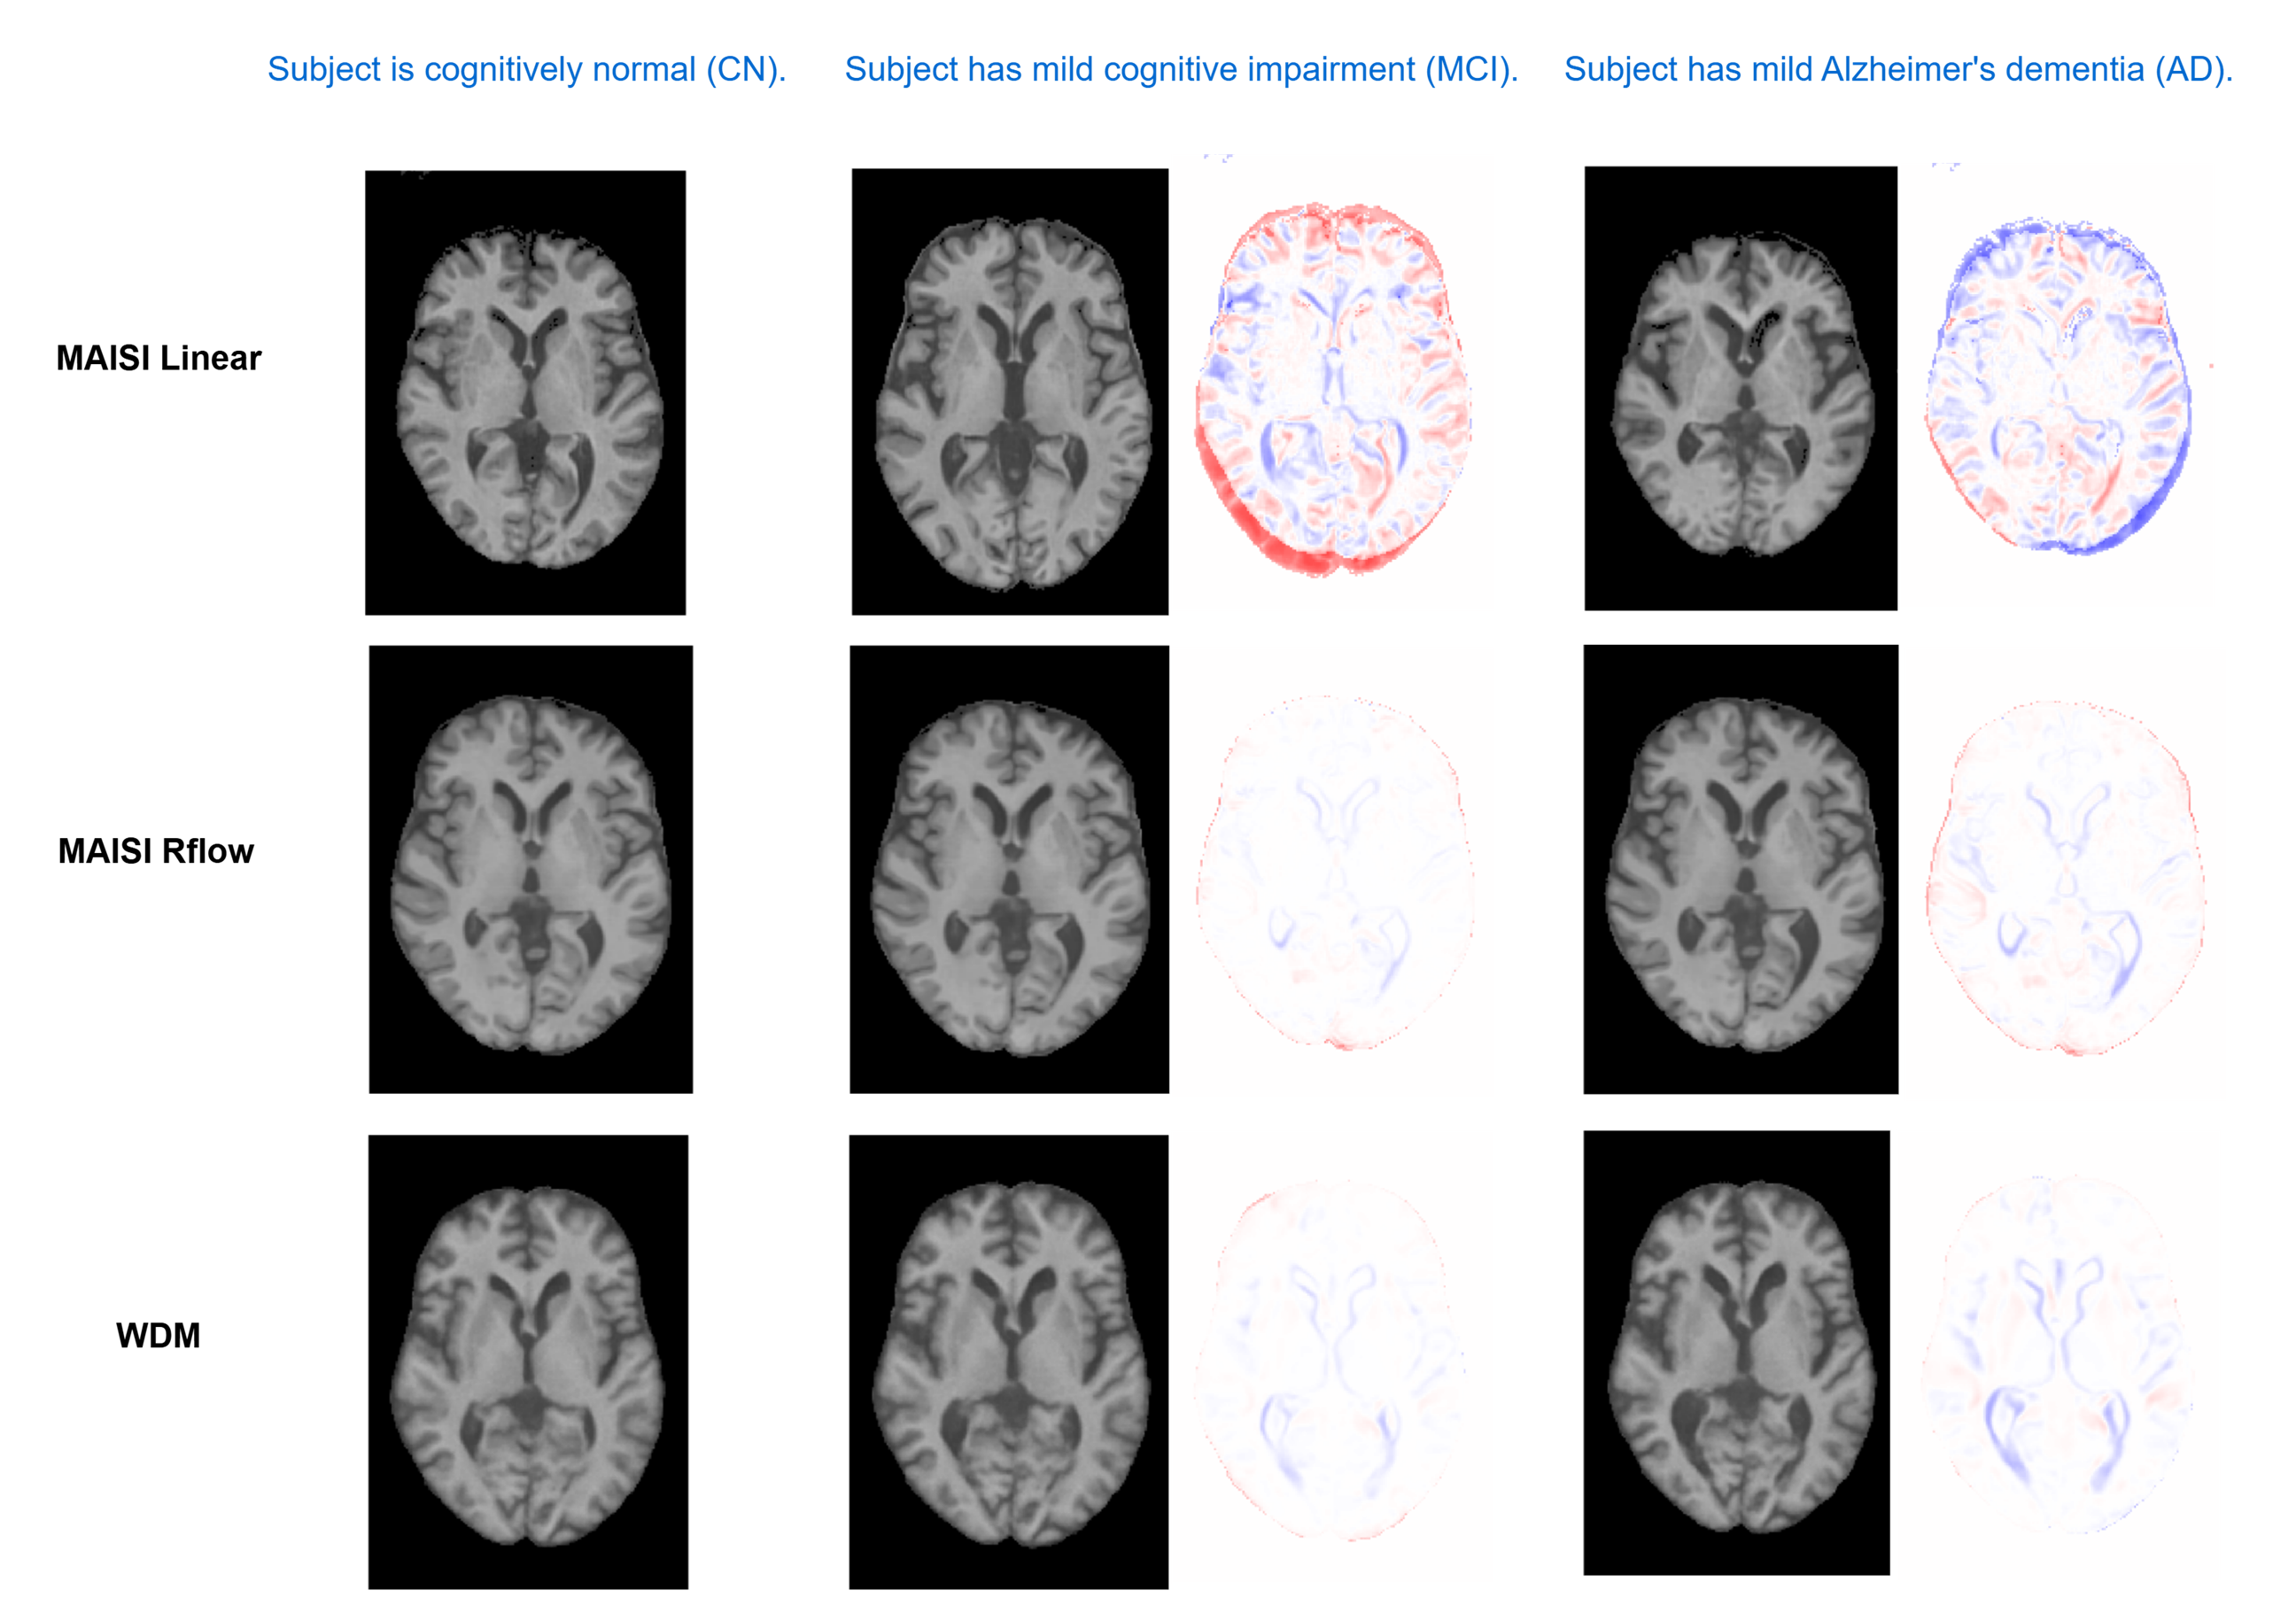

In this work, we introduced a novel vision-language framework designed specifically for generating high-resolution, text-guided 3D counterfactual medical images of synthetic neurological subjects. Our approach addresses critical limitations of existing methods by integrating advanced diffusion architectures with medically-informed semantic embeddings derived from BiomedCLIP. The results demonstrate that our language-guided wavelet-based diffusion model (WDM), operating directly in voxel space, delivers superior subject preservation, image quality, and text alignment compared to conventional latent diffusion approaches. Additionally, the MAISI RFlow model, which incorporates a Rectified Flow noise schedule, significantly improves anatomical consistency and image fidelity while achieving computational efficiency. Qualitative and quantitative analyses clearly indicate the effectiveness of these models in simulating nuanced disease-progression scenarios in synthetic patients, and our ablation studies on classifier-free guidance underscore the explicit trade-offs between prompt fidelity and anatomical accuracy.

Vision-language models have shown strong performance in 2D image generation due to extensive pretrained foundation models, but comparable models for 3D are lacking, limiting progress in medical imaging. This absence restricts applications such as counterfactual explanations, disease progression simulations, and medical training. We present a framework that generates high-resolution 3D counterfactual medical images from free-form language prompts by adapting state-of-the-art 3D diffusion models with enhanced text conditioning. To our knowledge, this is the first language-guided native-3D diffusion model applied to neurological imaging, enabling faithful representation of brain structures. Experiments on MRI datasets demonstrate the ability to simulate lesion loads in Multiple Sclerosis and cognitive states in Alzheimer’s disease, producing realistic images while preserving synthesized subject fidelity. Our work establishes a foundation for prompt-driven disease progression analysis in 3D medical imaging.